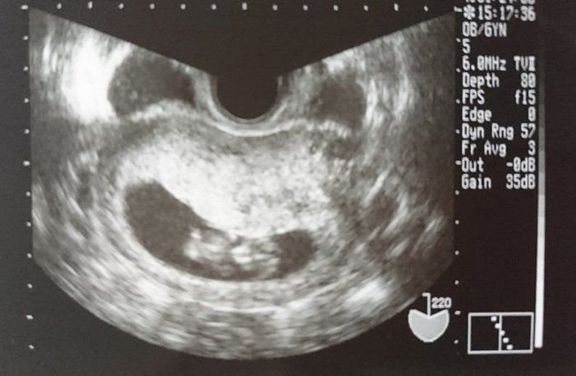

命の始まりは神秘的!2D・3D・4Dのエコー写真で見る「私と赤ちゃんの実録260日」 -

"おなかの中はどうなっていくの? エコー写真で振り返る、高齢ママのはじめての妊娠生活" -